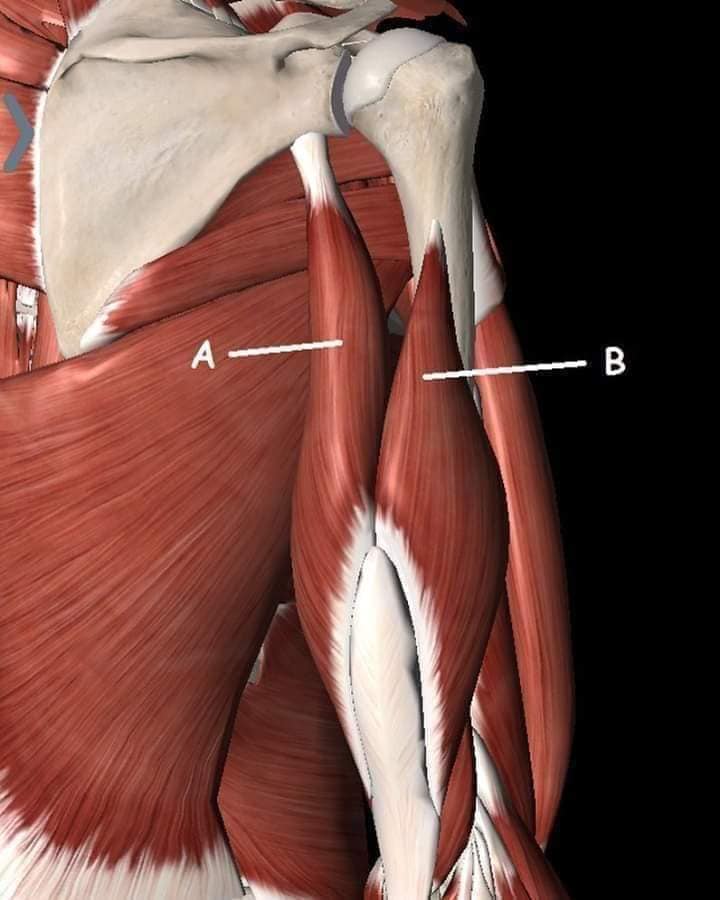

М'язи, що піднімають лопатку: Трапецієподібний м'яз: великий м'яз, що покриває верхню частину спини. Його функція - підтримка і рух лопаток, а також забезпечення стабільності хребта.

М'язи, що ведуть лопатку до хребта: Широкий м'яз спини: великий м'яз, що розташований в нижній частині спини. Він відповідає за рухи плечей і лопаток, а також за розширення верхньої частини тулуба.